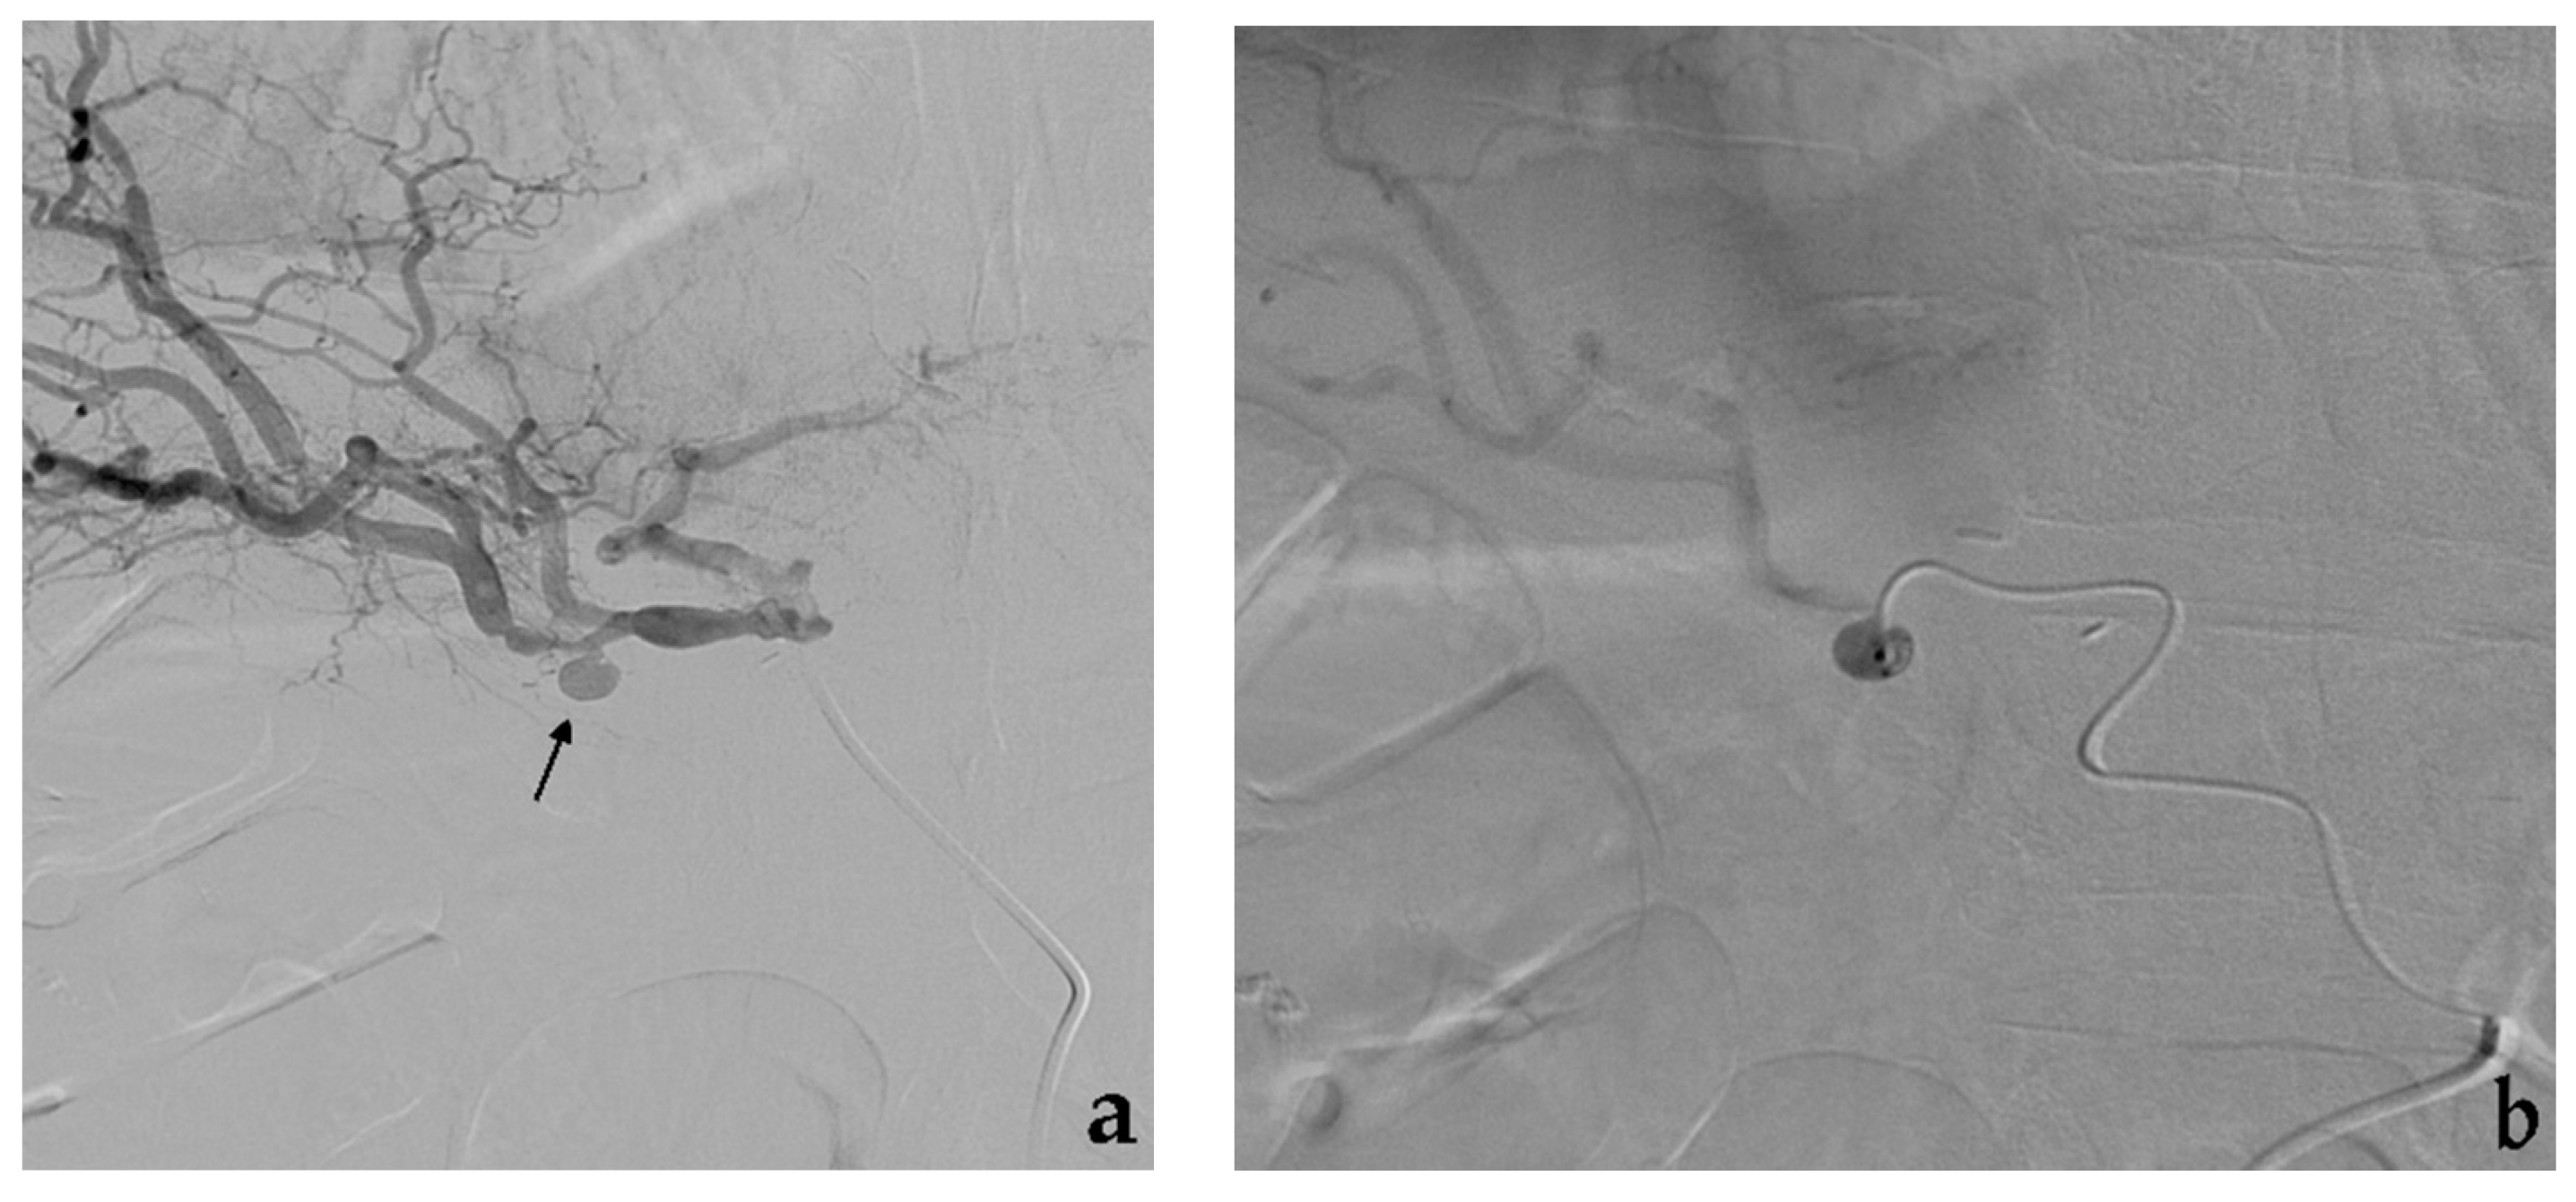

3.3. Balloon-Assisted Coil Embolization

- Modestino, F.; Cappelli, A.; Mosconi, C.; Peta, G.; Bruno, A.; Vara, G.; De Benedictis, C.; Golfieri, R. Balloon-assisted coil embolization of a wide-necked aneurysm of the inferior pancraticoduodenal artery. CVIR Endovasc. 2020, 3, 62. [Google Scholar] [CrossRef] [PubMed]

- Onal, Y.; Samanci, C.; Cicek, E.D. Double-lumen balloons, are they only useful in neurointerventions? Preliminary outcomes of double-lumen balloon-assisted embolization of visceral artery aneurysms. Vasc. Endovasc. Surg. 2020, 54, 214–219. [Google Scholar] [CrossRef]